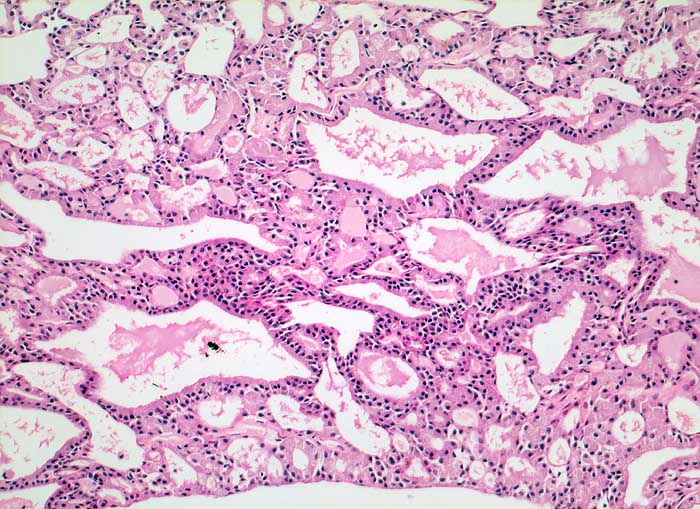

PathoPic ID 5446 - Azinuszellkarzinom

Azinuszellkarzinom

maligner Tumor

Parotis

Kopf & Hals, Sinnesorgane

An Schilddrüsenparenchym erinnerndes follikuläres Wachstumsmuster. Hochprismatische Tumorzellen mit kleinen Kernen und reichlich hellem Zytoplasma.

Histologie

100